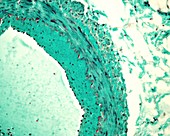

13613516 - Vein adventitia, light micrograph